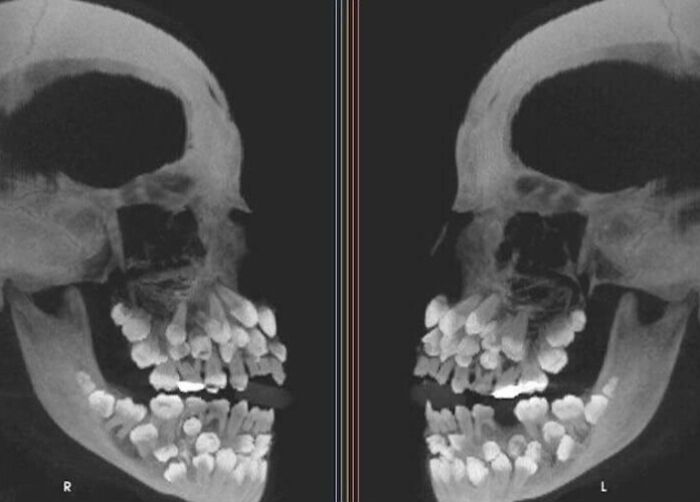

#4 An X-Ray Of A Person Who Has 3 Full Sets Of Teeth

Image credits: Poohbizzle79